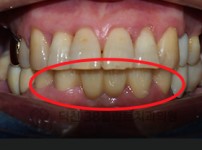

치료전후